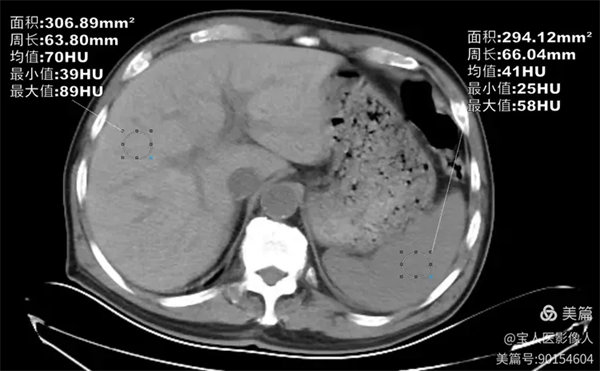

CT軸位,肝形態,大小正常,而CT值約70HU,較正常肝實質密度增高。